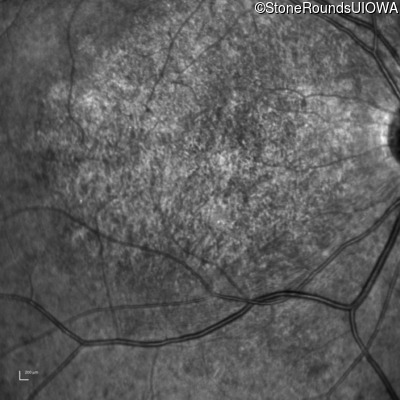

Infrared Fundus Photograph - Right - 20/200 -3 sc

Exemplar